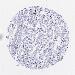

LIVER CANCER - Protein expressioni

A mouse-over function shows sample information and annotation data. Click on an image to view it in a full screen mode. Samples can be filtered based on level of antibody staining by selecting one or several of the following categories: high, medium, low and not detected. The assay and annotation is described here.

Note that samples used for immunohistochemistry by the Human Protein Atlas do not correspond to samples in the TCGA dataset.

Antibody stainingi

Antibody staining in the annotated cell types in the current human tissue is reported as not detected, low, medium, or high, based on conventional immunohistochemistry profiling in selected tissues. This score is based on the combination of the staining intensity and fraction of stained cells.

Each image is clickable and will lead to virtual microscopy that enables deeper exploration of all samples and also displays staining intensity scores, fraction scores and subcellular localization as well as patient and tissue information for each sample.

Antibody HPA022132

Antibody HPA052381

Antibody CAB002493

Antibody CAB025255